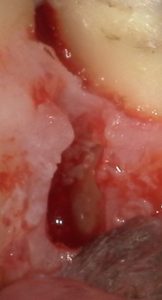

【外科的根管治療 頬側の骨がすでに吸収していて遠心側の歯根が露出している】